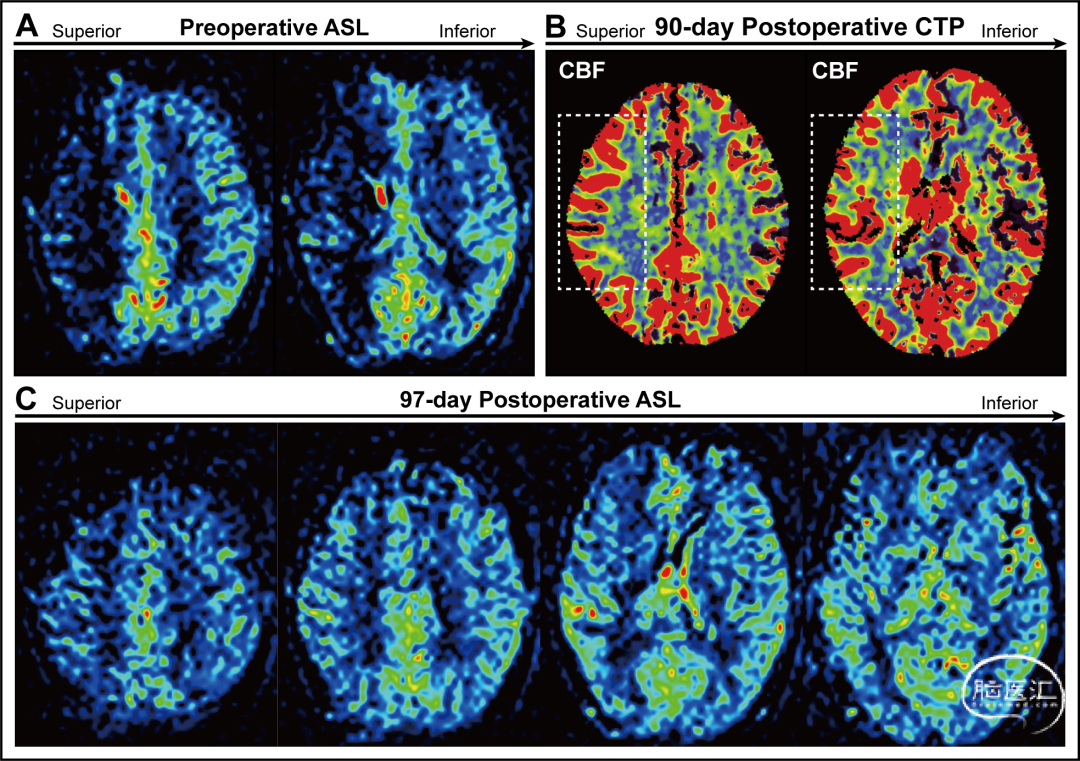

一名36岁女性,因持续性头痛检查发现右侧颈内动脉多发动脉瘤伴一枚巨大动脉瘤,成功植入FD(图1. A),术后两个月,患者头痛症状消失。术后3个月,患者再次出现头痛和视力问题,因此进行数字减影血管造影( Digital subtraction angiography, DSA)随访,以评估动脉瘤愈合情况(图1. B)。术前动脉自旋标记(Arterial spin labeling, ASL)显示右侧大脑半球的灌注水平低于左侧(图2. A)。术后90天的CT灌注成像显示右侧大脑半球灌注较左侧增加(图2. B)。经降血压和脱水治疗后,患者头痛得到缓解,术后97天的ASL图像显示双侧灌注对称(图2. C)。

图2. 灌注图像。A:术前ASL显示右大脑半球的灌注明显低于左侧。B:术后90天的CT灌注成像脑血流图(CBF)。C:术后97天ASL影像学显示双侧大脑半球灌注基本对称。